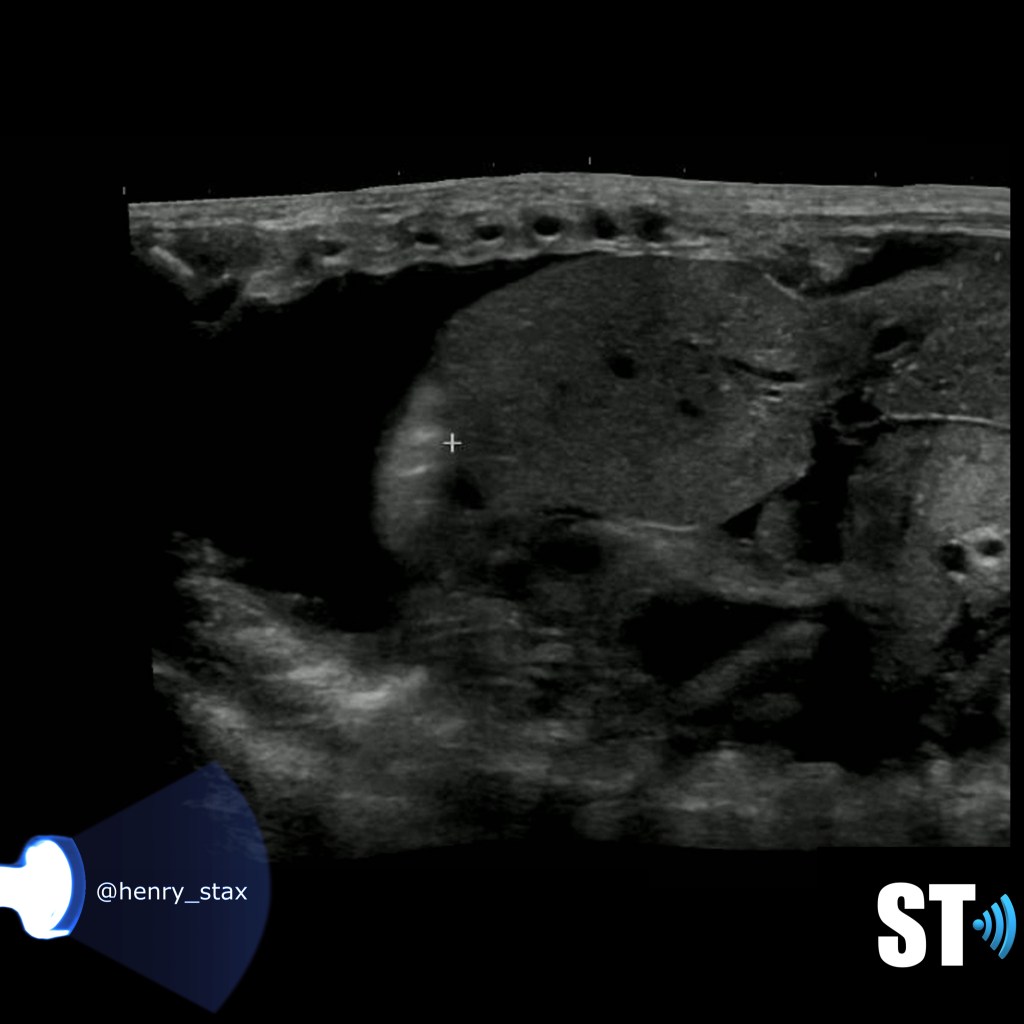

Right sided sarcoma with pleural effusion

Right chest sarcoma with pleural effusion